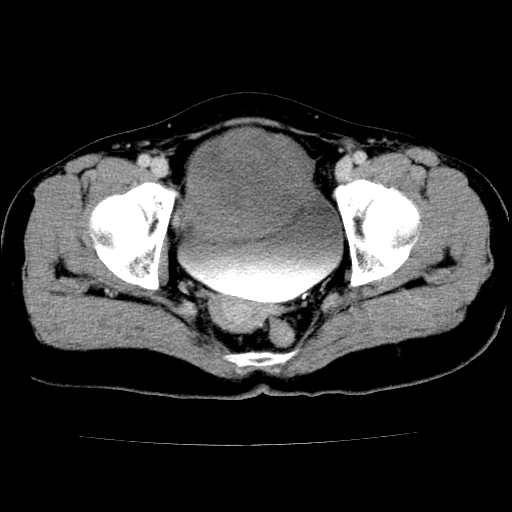

标题: CT24785:女,62岁,发现下腹部肿物半年。 [打印本页]

标题: CT24785:女,62岁,发现下腹部肿物半年。

女,62岁,发现下腹部肿物半年,下腹部不适。

卵巢囊腺瘤或囊腺癌,建议免疫组化实验

卵巢囊腺瘤或囊腺癌可能。

考虑附件囊腺癌。

考虑卵巢囊腺瘤或囊腺癌可能。